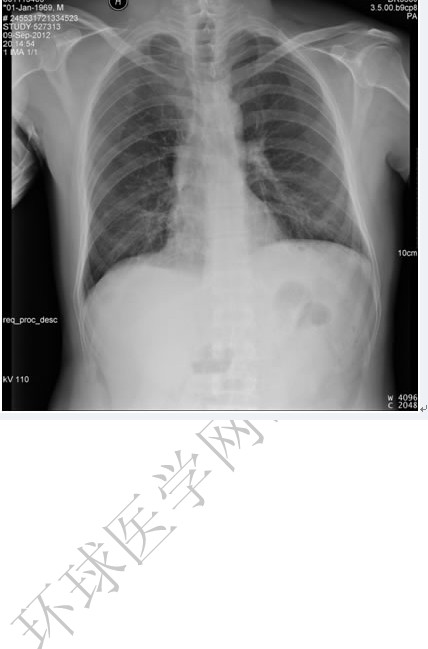

后肋骨折

图示为右侧3,5,6,7,8后肋骨折。

(1)后前位